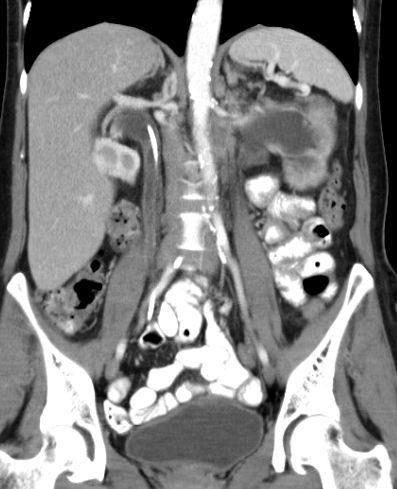

| paraaortale Lymphknoten - Metastasen |

![]() Großes Lymphknotenkonglomerat links paraaortal. Vergrößerte Lymphknoten an der linken Beckenwand. |

![]() 2 große Lymphknoten links zwischen Aorta und Musculus psoas. | ||